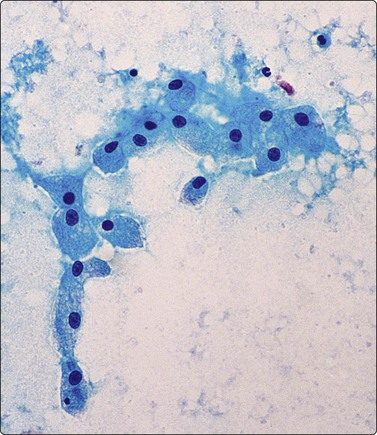

A high polymorph content is usually present in the inflammatory reaction to fungi. A search for a granulomatous component and fungal organisms is mandatory if acute inflammatory material is obtained. With infection by filamentous organisms, e.g. Nocardia, the organisms may be identified in the center of distinctive, cohesive neutrophil clusters or rosettes after silver impregnation; this clustering should be a clue to search for such an infection (Fig. 8.4). Similar appearances may also be be seen in streptococcal infection.

image image

Fig. 8.4 Neutrophil rosette

(A) Clump of neutrophils (H&E, HP oil); (B) Fine branching filaments of Nocardia (Methemamine silver, HP oil).